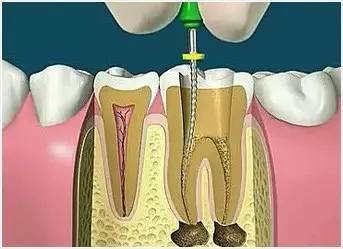

5、根管冲洗、消毒

根管冲洗的目的是清除微生物、冲掉残渣,润滑根管器械和溶解有机残渣。然后,再进行根管消毒,使根管内达到无菌状态。

6、根管充填

封闭整个根管系统、堵塞主根管和侧副根管出口、防止微生物和液体的渗漏。无论是侧方加压法还是垂直加压法,应做到根管充填致密,根管充填后X线片上无根管腔隙,也不能超出根尖孔。